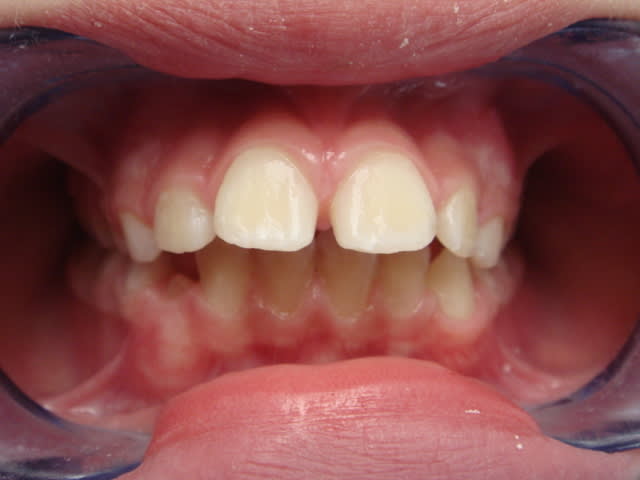

petit fille (10 ans)qui n'a soit disant jamais sucé son pouce (j'en doute) vu la poussée du prémaxillaire) ou magnifique travail de la langue

et maman vient pour que l'on remettre les incisives de la petite à leur place, petite exigeance , elle ne veux rien de fixe, mais je pense pouvoir eventuellement la convaincre.

que ce soit succion du pouce ou de la levre inf ou de la langue,peu importe

il doit y avoir aussi perturbation de la phonation et de la deglutition

respiration buccale

Apres,pff, c'est du banal, on a de la classe 1 molaire, une proalvéolie sup ,pas de ddd apparente (faudrait peut etre quand meme indicer un chouia). Elastics,torquez, mada, elastics, torquez mada, elastics.et encore du torque.

Dans un cas comme celui-ci où il n’y a qu’une bascule palatine des incisives supérieures à réaliser, l’avantage majeur de l’appareillage fixe est de permettre une correction de la mésio-vestibulo-rotation des molaires supérieures et ainsi de gagner de la place en latéral. Autrement, n’importe quel système mobile bien pensé devrait pouvoir faire l’affaire : la plaque épaisse d’Annie, le mobile d’Hordeotech ou les Soulet-Besombes de Catrose…